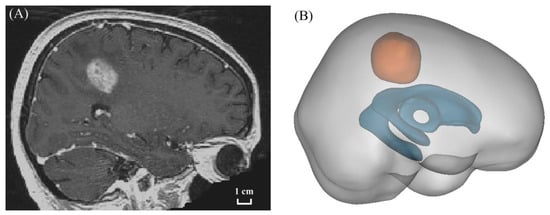

2.2. Model Geometry